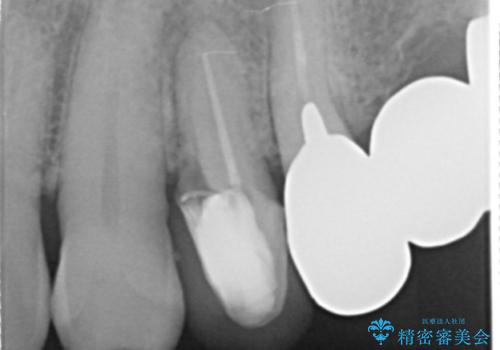

精査したところ、歯ぐきが腫れている左上の小臼歯(左上4)は保存不可能な状態でした。

保存不可能な歯(左上4)を抜去後、ブリッジによる補綴治療を行いました。

- ¥760,000 (根管治療×2本、土台×2本、仮歯×5本、クラウン×5本)費用は治療当時の料金となります